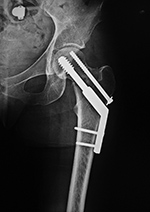

A special type of screw used in the treatment

of intertrochanteric proximal femur fractures

is called a dynamic compression screw (device) consisting of a large lag screw with

distal threads that is inserted into the femoral

head and neck. This screw fits into the barrel of a

side plate, which is secured to the femoral shaft

with multiple cortical screws. The lag screw can

slide within the barrel, which results in compression

of the fracture site as the patient ambulates (figure: hip dynamic compression screw)

(Ruedi, 2007; Benjamin, 1994; Berquist, 1995; Freiberg, 2001; Hunter, 2001). If the fracture settles, the lag screw slides within the barrel preventing the screw from piercing the femoral head and entering the hip joint space.

| Dynamic compression hip screw |

Dynamic compression hip screw, partially threaded cannulated cancellous fixation screw and washer |

Dynamic compression hip screw

|

| There is also a partially threaded cannulated cancellous fixation screw. |